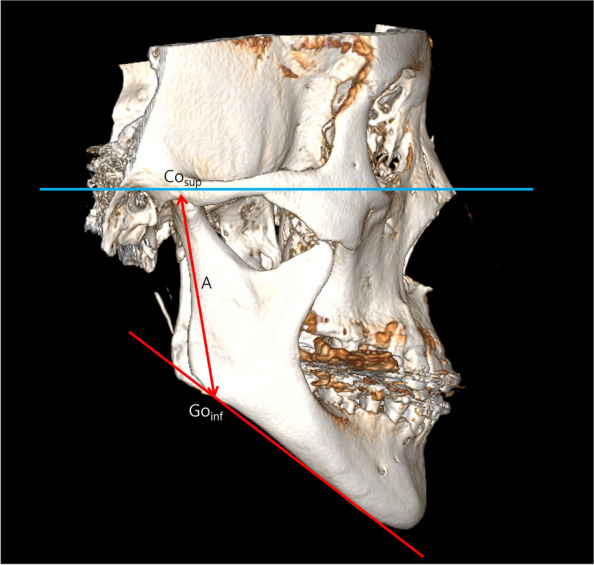

Methods: This retrospective cohort study investigated patients who underwent mandibular setback surgery using bilateral sagittal split ramus osteotomy. Three-dimensional CT scans were taken at three different time points. Evaluation of the postoperative stability involved measuring changes in the x, y, and z axes as well as roll and yaw rotations of the mandible at specific landmarks (B point, mental foramen) on 3D CT scans obtained immediately after surgery and 6-12 months postoperatively. They were categorized into four groups based on bilateral mandibular height asymmetry through Asymmetry index (AI). The one-way ANOVA was implemented to compare the intergroup differences and Tukey's post hoc test was employed. Additionally, the Pearson correlation coefficient was also calculated.

Results: A total of 24 patients were included in this study. The corresponding AI, representing the degree of asymmetry in both mandibles, were calculated as Group 1 was 1.25 ± 0.64%, Group 2 was 2.89 ± 0.47%, Group 3 was 5.03 ± 0.51%, and Group 4 was 9.40 ± 1.99%. The x-axis change in Group 4 was significantly larger at 1.71 mm compared to Group 1 at 0.64 mm. The mandibular roll, Group 4 showed a statistically significant increase at 1.33° compared to Group 1 at 0.35°. And there was a significant positive correlation observed between x-axis change and AI (p = 0.019), as well as between mandibular roll and AI (p = 0.025).